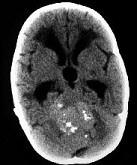

成年男性,头痛、头晕、恶心,病程二年余,结合影像图像选择最可能的诊断()A.脑膜瘤B.星形细胞瘤C.室管膜瘤D.胶质瘤E.畸胎瘤

问题 成年男性,头痛、头晕、恶心,病程二年余,结合影像图像选择最可能的诊断()

选项 A.脑膜瘤 B.星形细胞瘤 C.室管膜瘤 D.胶质瘤 E.畸胎瘤

答案 C